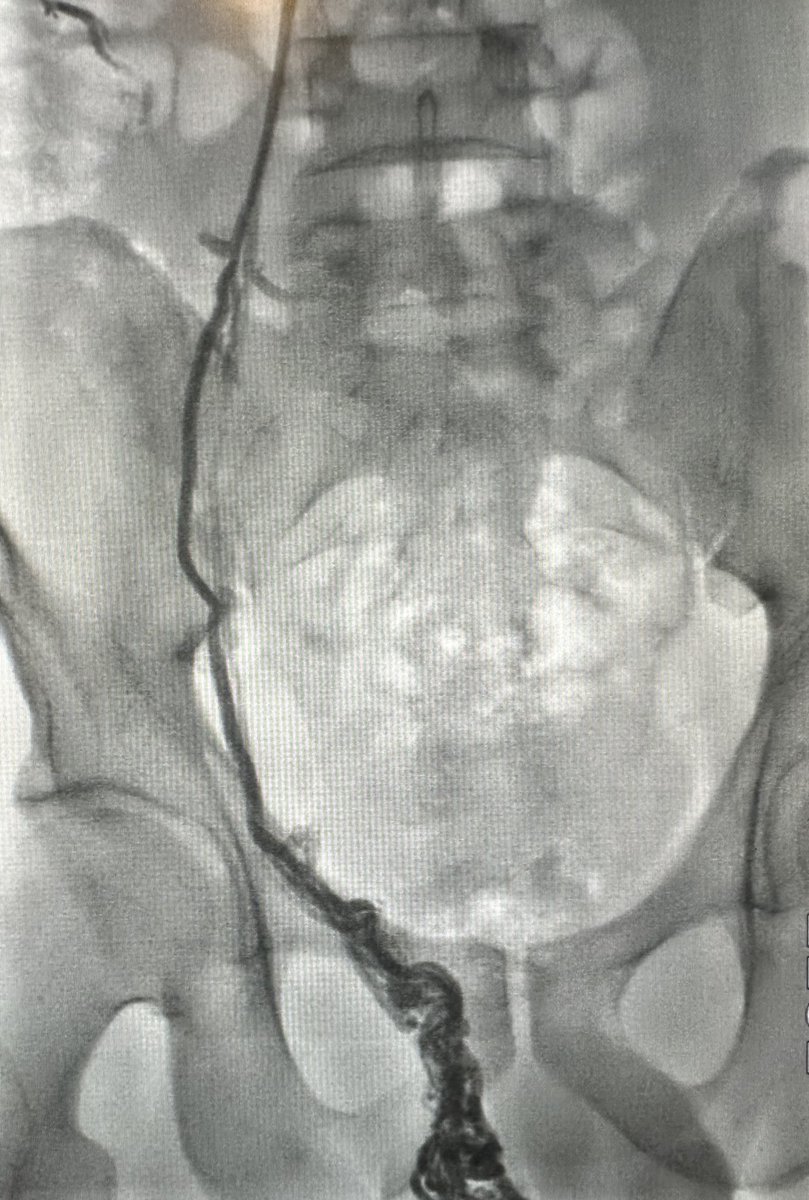

طريقة تغلغل الصمغ الطبي في علاج الأوردة المغذية لدوالي الخصية بالقسطرة. اغلاق جميع الأوردة بدون المساس بالقنوات الليمفاوية (فلا يحصل قيلة مائية) ولا الشعيرات الشريانية الدقيقة (فلا يحصل ضمور) القسطرة والأشعة التداخلية اثبتت بالابحاث افضليتها على الجراحة من كل النواحي

علاج دوالي الخصية بالأشعة التداخلية ، العلاج بالصمغ الطبي يعتبر أفضل وأحدث علاج. يتم إغلاق الدوالي والأوردة بدقة دون التعرض للشرايين والقنوات الليمفاوية الدقيقة. مثال لمريض لديه ما يفوق عن ٤٠ وريد ، لا يمكن ربطها جميعاً جراحياً. بالقسطرة؟ انتهينا من الجهتين خلال اقل من ١٠ دقائق.

لولا وجود الندبة الجراحية لما صدّقت. مريض سبق وأن عمل عملية دوالي خصية مجهرية (مايكروسكوب) وبالطبع لم يتم علاجها بالشكل الصحيح. الأشعة التداخلية وضحت دوالي مهولة من ناحية العدد والحجم… لماذا يتعرض المريض للعملية بمخاطرها (ضمور صامت بنسبة ١ من كل ١٤٠ مريض أو قيلة مزمنة بنسبة ١-٢